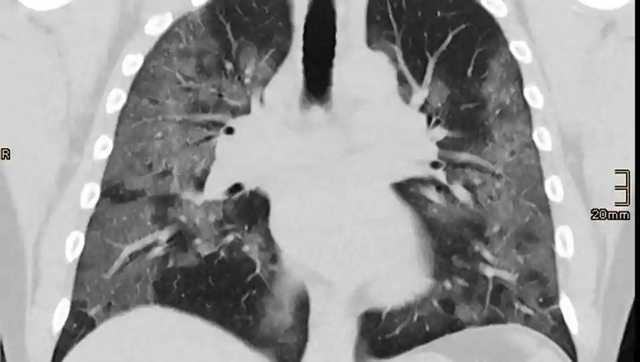

Исследования показали, что у 70% переболевших коронавирусом людей через четыре месяца после выздоровления наблюдаются поражения внутренних органов. В исследуемой группе были молодые люди с низкой распространённостью сопутствующих заболеваний.

Через четыре месяца после инфицирования у 70% переболевших обнаружены нарушения одного или нескольких внутренних органов.

В обследовании участвовали 200 человек со средним возрастом 44 года. Оценку состояния проводили через 105-160 дней после появления у них симптомов коронавируса.

Через несколько месяцев после появления первых симптомов коронавируса у участников все еще наблюдались кардиореспираторные (92%) и желудочно-кишечные (73%) поражения, а у 42% людей было десять или более поражений различных органов, — сообщили учёные.

Исследователи утверждают, что были доказательства легкого поражения органов сердца (32%), легких (33%), почек (12%), печени (10%), поджелудочной железы (17%) и селезенки (6%).